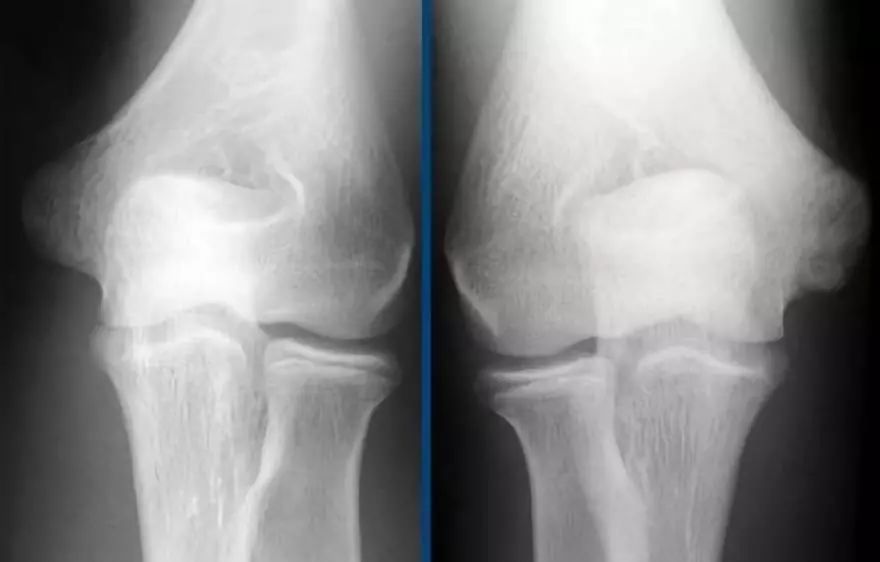

小联盟球员的手肘(Little Leaguer’s Elbow):患臂内上髁骨质减少。

在这些情况下,我们通常会要图像求比,因为它可能非常细微。诊断是Little leaguer的肘部是由慢性压力损伤引起的。在X射线照片,它看起来像一加宽的骨骺线,是由于在干骺端软骨向内生长。

● 在MR上,异常非常明显。内侧上髁和相邻骨中存在骨髓水肿(黄色箭头)。● Little Leaguer的肘部也被称为内侧性上睑下垂,有些人称之为骨骺溶解。● 顺便说一下,如果是急性创伤事件,这也可以称为Salter-Harris I型骨折。● 注意正常的尺侧副韧带(红色箭头)。在儿童中,外翻应力的薄弱环节不是尺侧副韧带,而是骨骺。

下面是另一种情况。这个病人年龄偏大。左上髁已经融合,但在右边,古河仍然有点开放。

在MR上有骨髓水肿。请注意,尺侧副韧带附着也有一些水肿,所以也有一些UCL的撕裂。